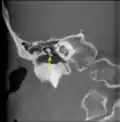

Scanner en coupe coronale montrant un malleus- Dissection montrant les 3 osselets de la chaine ossiculaire retirés de la cavité tympanique.